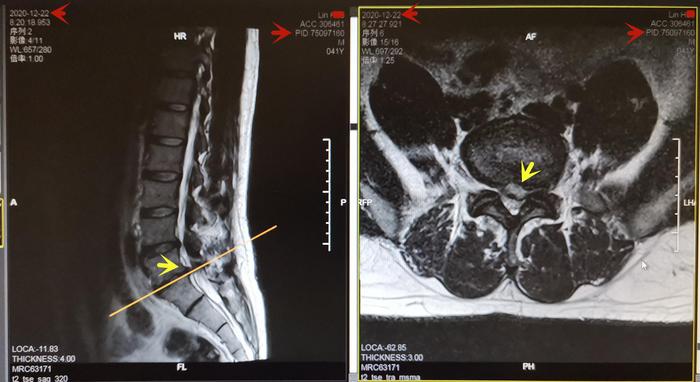

Lin先生,42岁,202011月腰及左下肢麻痛1月。此前反复发作左肩背、腰痛4年,急性发时不能起床,有一次用救护车送医院。检查身体:L5-S1间隙、左臀部及下肢压痛,左下肢腿抬高试验阳性,左踇背痛觉减退,左足背外侧痛觉减退,左踇背伸肌力减弱至3-4级,左跟腱反射减弱,神经受压损伤,诊断为“腰椎间盘突出症”。20201222日核磁共振:L5-S1椎间盘向左后外侧巨大突出,压迫神经根,见图7。建议患者微创治疗之后功能训练,患者拒绝手术治疗要求功能训练。经过每周13个月的训练后,患者的下肢麻痛基本消失,腰骶部疼痛明显减轻。又过2个月左下肢麻痛及不适消失。检查身体:左侧腰L5-S1轻压痛,双下肢直腿抬高试验恢复正常,左踇背痛、触觉基本恢复正常,双下肢肌力和生理反射恢复正常。20211224日复查腰椎核磁共振:L5-S1左侧突出的椎间盘基本消失,神经根受压解除,见图8。继续维持训练避免了复发加重,恢复工作生活,图9

图7. Lin先生2020年12月22日L5-S1椎间盘左侧巨大突出压迫神经根,黄色箭头。